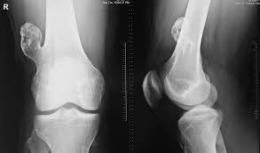

Η εικόνα απεικονίζει περιστατικό με ανευρυσματική κύστη στο μηριαίο, το

οποίο χειρουργήθηκε από τον Δρ. Ζένιο. Διενεργήθηκε καθαρισμός της κύστης, τοποθέτηση μοσχεύματος

και υλικό οστεοσύνθεσης.